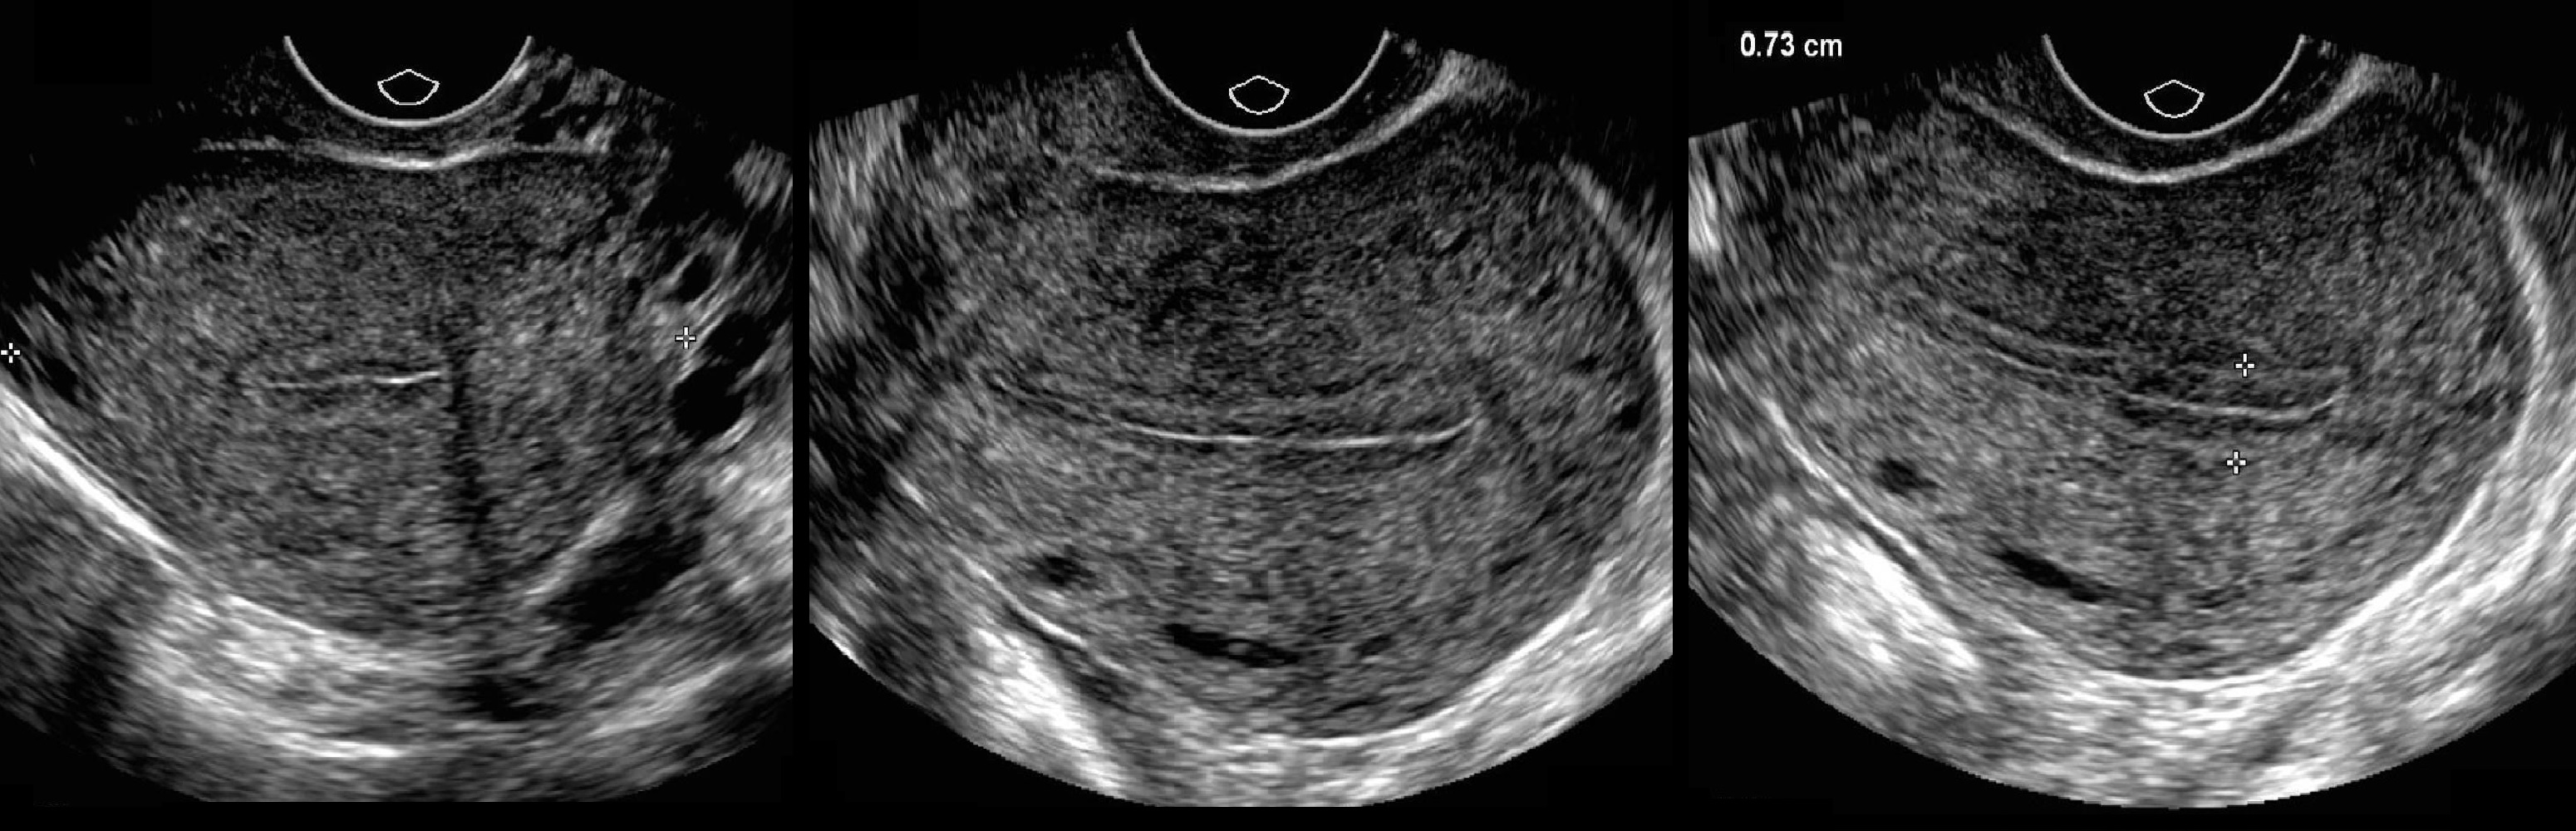

Анатомия женского организма: строение и функции матки